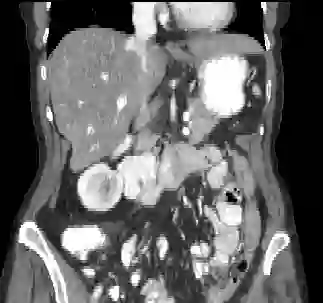

Recently, deep learning methods have achieved state-of-the-art performance in many medical image segmentation tasks. Many of these are based on convolutional neural networks (CNNs). For such methods, the encoder is the key part for global and local information extraction from input images; the extracted features are then passed to the decoder for predicting the segmentations. In contrast, several recent works show a superior performance with the use of transformers, which can better model long-range spatial dependencies and capture low-level details. However, transformer as sole encoder underperforms for some tasks where it cannot efficiently replace the convolution based encoder. In this paper, we propose a model with double encoders for 3D biomedical image segmentation. Our model is a U-shaped CNN augmented with an independent transformer encoder. We fuse the information from the convolutional encoder and the transformer, and pass it to the decoder to obtain the results. We evaluate our methods on three public datasets from three different challenges: BTCV, MoDA and Decathlon. Compared to the state-of-the-art models with and without transformers on each task, our proposed method obtains higher Dice scores across the board.